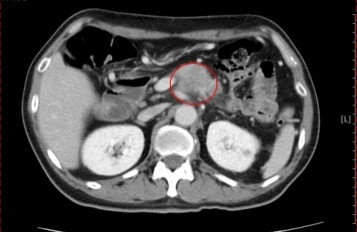

5旬男長期酗酒又有糖尿病 查出罹胰臟癌2期

2026/04/13 19:5652歲男性有糖尿病史,近1個多月持續腹部悶痛,竟被查出胰臟腫瘤達3.5公分(2期),澄清醫院內分泌科主任林幸宜表示,糖尿病患者若有酗酒習慣,誘發胰臟癌風險可能增加2倍,尤其新發糖尿病會誘發胰臟疾病,呼籲保持良好血糖控制,不僅能降低罹癌風險,也能減輕癌症併發症、提高存活率。